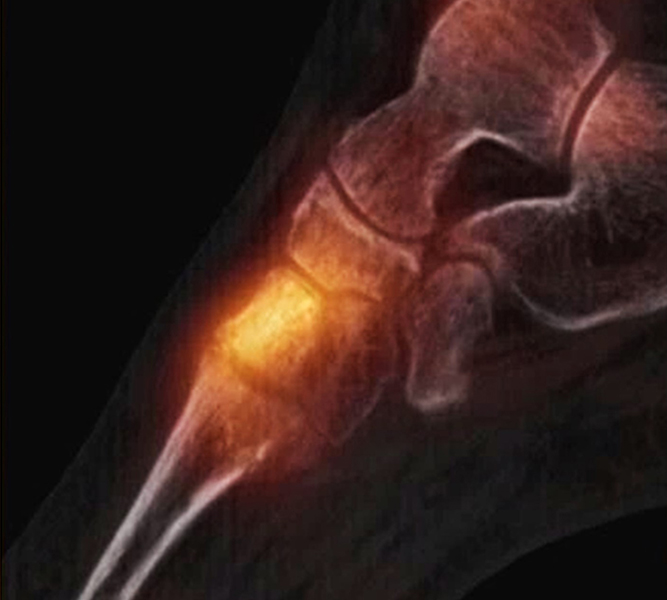

Abbildung 8.8.a bis d: Patientin mit bekanntem Knick-Senk-Fuß. Anamnestisch Schmerzen in beiden Füßen, links > rechts seit ca. 2 Jahren. Fragestellung: Status der bekannten Fußwurzelarthrosen vor geplanter OP. Neben, unter anderem fortgeschrittenen Arthrosen im Naviculo-Cuneiforme-Gelenk, Nachweis einer Tibialis posterior-Sehnen-Tendinitis mit begleitender Periostitis/Ostitis am Malleolus postero-medial. Abbildung 8.8.a und b: in der Frühphase (2 Minuten nach Tracerinjektion) sind lineare Anreicherung des Tracers im Verlauf der linken Tibialis posterior Sehne zu sehen.  In der  Mineralisationsphase im SPECT/CT begleitende Periostitis/Ostitis am Malleolus postero-medial. Abbildung 8.8.c und d: Der Blick auf das CT im Weichteilfenster offenbart diffuse entzündliche Verdickungen im Verlauf der linken Tibialis posterior Sehne. Rechts unauffälliger Befund. Unten beispielhaft die schmerzhafte NC-Arthrose.

Abbildung 8.9. a bis c: Extern MRT-morphologisch V. a. Coalitio calcaneo-naviculare. Anamnestisch Schmerzen im linken OSG seit ca. 1,5 Jahren, gehäuftes „Umknicken“ des linken Fußes, Pes planus bds.. Abbildung 8.9.a zeigt die 3D-Früh-SPECT aus verschiedenen Blickwinkeln. Wie in Abbildung 8.8.a findet sich hier eine deutliche lineare Tracerakkumulation im Verlauf der linken Tibialis posterior Sehne. Abbildung 8.9.b: In der Mineralisationsphase wie auch im vorhergehenden Fall ossäre Reaktion postero-medial am Mallelolus medialis als Zeichen einer chronischen Tendinitis. Die Durchsicht der 7 Wochen zuvor angefertigten externen MRT bestätigte den Befund (er war leider nicht beschrieben worden). Im SPECT/CT wurde eine Coalitio ausgeschlossen.

Abbildung 8.10.a bis e: Patient mit Verdacht auf symptomatisches Os peronaeum. In der Früh-SPECT/CT eindeutiger Nachweis einer ausgeprägten Tendinitis der Peronealsehnen links. In der Mineralisationsphase Stessreaktion im Bereich eines mehrgeteilten Os peroneaum links und lateral Calcaneus.